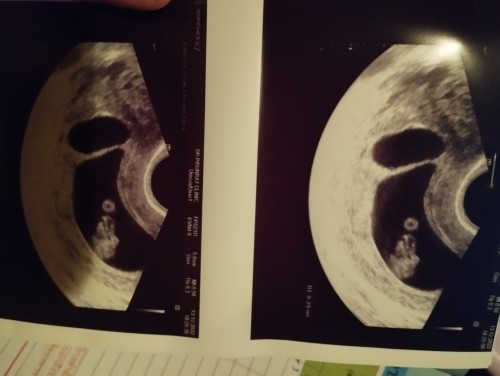

สอบถามคะ พอดีไปซาวมาเมื่อวาน 8สัปดาห์ คุนหมิบอกเห็น2ถุง มีสิทธ์จะได้แฝด แต่อีกถุงมีขนาดเล็ก และมีสิทฝ่อ มีใครเคยเกิดเหตุการณ์แบบนี้บ้างมั้ยคะ